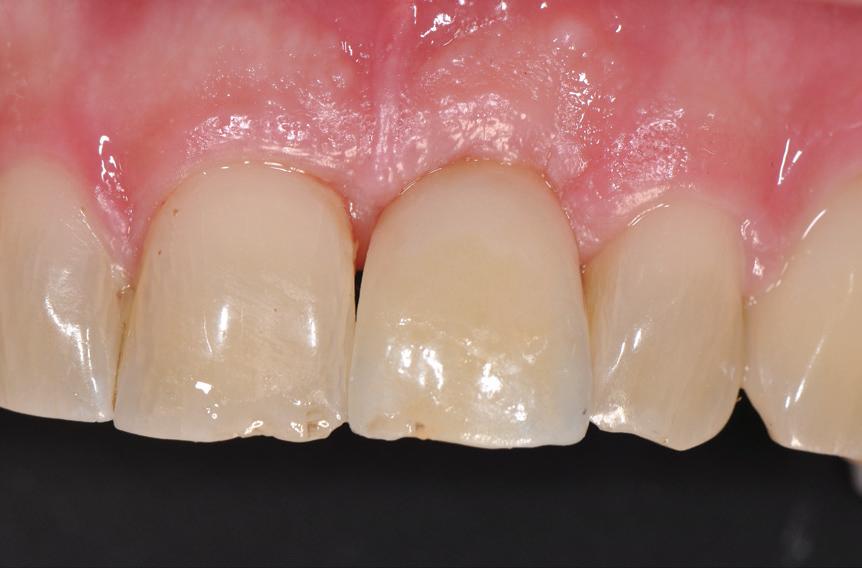

SITE AUGMENTATION Reconstituirea țesutului moale periimplantar și papilar în zona estetică

RECONSTITUIREA țesuturilor moi periimplantare. Scopul acestui raport de caz este de a demonstra procedurile chirurgicale utilizate pentru corectarea unui defect al țesuturilor moi periimplantare folosind țesutul moale interdentar în combinație cu tuberozitatea ca locație donatoare de țesut conjunctiv, utilizând o abordare prin tunelizare într-o zonă estetică.